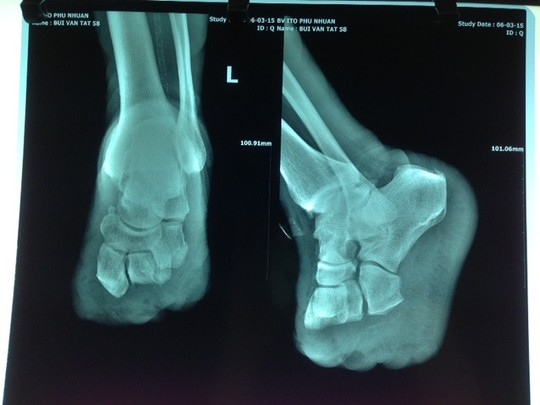

Sau đó một thời gian, chị thấy người mệt mỏi, nhiều lần nằm ngủ chị thấy khó thở, bàn chân nóng và tê. Chị đi kiểm tra sức khỏe bác sĩ cho biết chị bị tiểu đường. Điều trị bệnh 1 năm thì tiểu đường biến chứng sang suy thận.